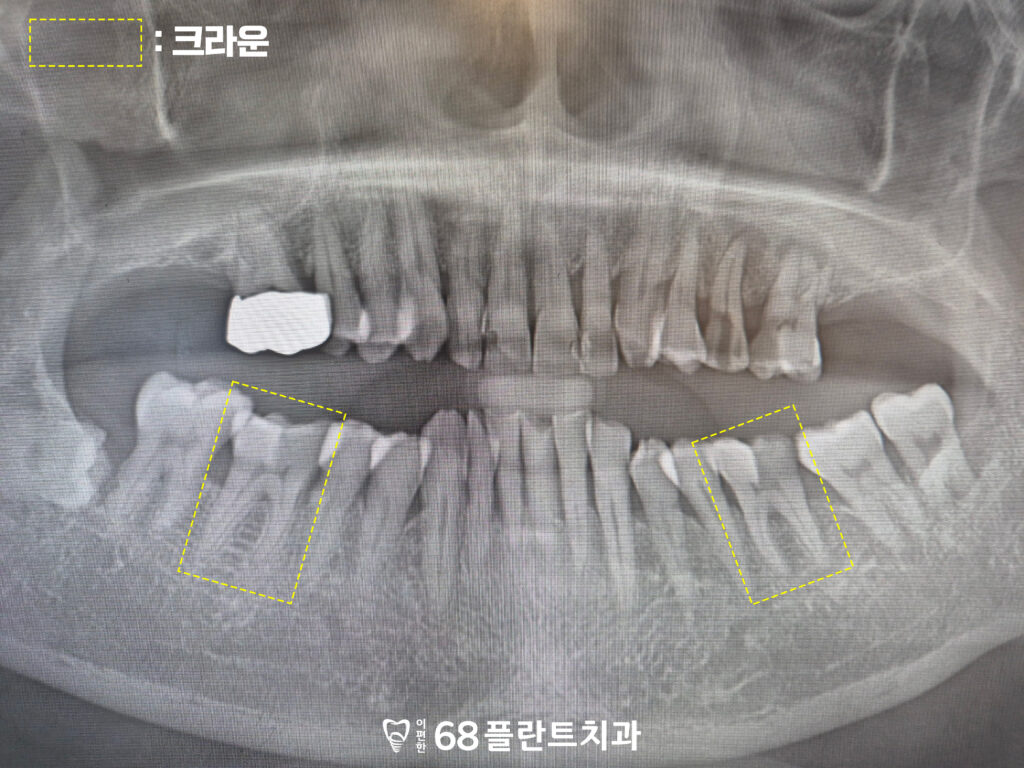

19.11.20

또한 환자분께서 씹는 힘이 강하셔서

치아가 마모가 되어있기도 하고

이러한 힘이 지속적으로 가해져

아래 치아도 불편한 상황이였습니다.

그래서 해당 치아들은 크라운으로

치아를 보호하여 과도한 교합력으로부터

약해진 치질을 감싸고

기능을 안정시키는 방향으로

치료를 진행하기로 했습니다.

크라운은 마모가 심하거나

뿌리 치료 이후 약해진 치아를

보호하는 데 도움이 되며,

특히 씹는 힘이 강한 분들에게는

치아 균열·파절을 예방하는

중요한 역할을 합니다.